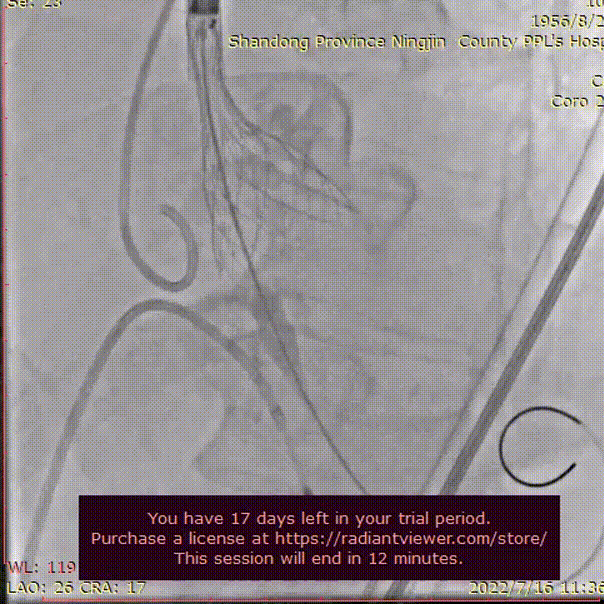

行冠脉造影,LM末端50%狭窄,PDA近中段50-60%狭窄,中段90%狭窄,LCX近中段60-70%狭窄,RCA全程50-70%狭窄,PDA近中段50-60%狭窄,前向血流均为TIMI3级。

左冠脉造影

右冠脉造影

使用3.0*23mm支架处理病变位置,支架植入后造影显示血管灌注良好。

LAD冠脉支架植入

支架植入后评估

行主动脉根部造影,猪尾确定选择最佳释放体位,观察瓣叶活动,选择合适体位跨瓣。

主动脉根部根部造影

球囊预扩

术者团队用22mm球囊预扩,结合瓣环及球囊预扩情况,预装AV26型号瓣膜。

输送器过弓

初始定位

术者结合DSA影像,多角度观察瓣膜情况,瓣膜释放至工作位造影评估并最终释放。

释放至工作位

完全释放

无明显返流,瓣膜形态佳,工作稳定。手术顺利结束。